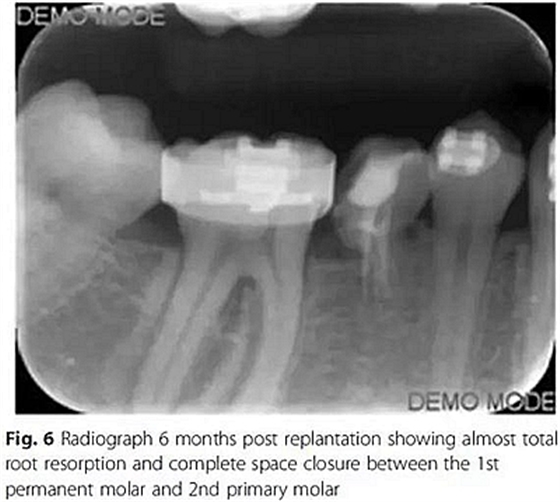

10周后,根據(jù)臨床和影像,形成乳磨牙牙槽粘連,移除牙弓夾板。下一步,在右下第一磨牙上粘接帶環(huán),在第二乳磨牙和下頜第一前磨牙上粘接托槽,在恒磨牙和乳磨牙之間安裝T型曲前移第一恒磨牙。T型曲共激活9次。

第6個(gè)月,臨床和影像檢查顯示乳牙幾近完全的替代性牙根吸收和間隙的完全關(guān)閉。最終,將乳磨牙拔除并開(kāi)始進(jìn)行完整的正畸治療。在接下來(lái)一年,用0.017’’*0.025’’末端回彎的不銹鋼弓絲和彈性牽引剩余間隙關(guān)閉,并以II類牽引作為支持。